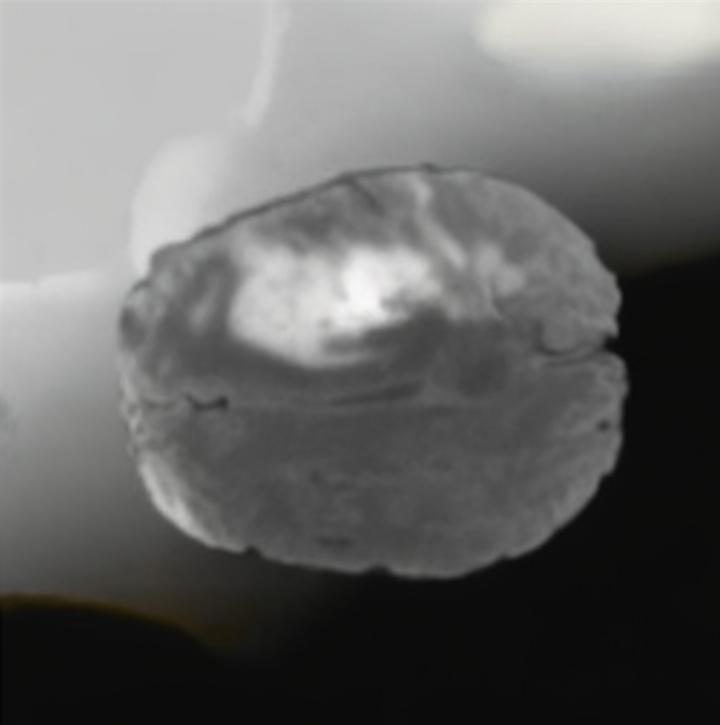

Our results unequivocally highlight the superior performance of X-Diffusion in terms of both qualitative and quantitative metrics. Representative MRI volumes generated by our pipeline, when juxtaposed with ground-truth images, showcased remarkable similarity, with even intricate physiological features like tumor information, spine curvature, and fat distribution being accurately captured.

Notably, X-Diffusion achieves sota dB for a few input slices while baselines require more than 60 input slices to achieve similar performance (Figure 7). The margin is more than 12 dB PSNR for the 1-slice input in both the BRATS and the UK Biobank benchmarks (see Table 1 and Figure 6). For reference, two randomly sampled MRIs from the UK Biobank would have a PSNR of 15.95 dB 0.36 (on 4800 randomly sampled examples). The slices from 3D reconstructed volumes at varying depths and axis of rotation visually match the ground truths (see Figures 5 and Figure 4). We also plot the error map (Figure 4) of such X-Diffusion generations to highlight the differences with the ground truth MRIs.

The comparison of generated MRIs versus reference MRIs suggests a nearly perfect preservation of brain volume (in mm3) with median volume of reference MRIs of versus generated MRIs (see an example of brain generation in Figure 11).